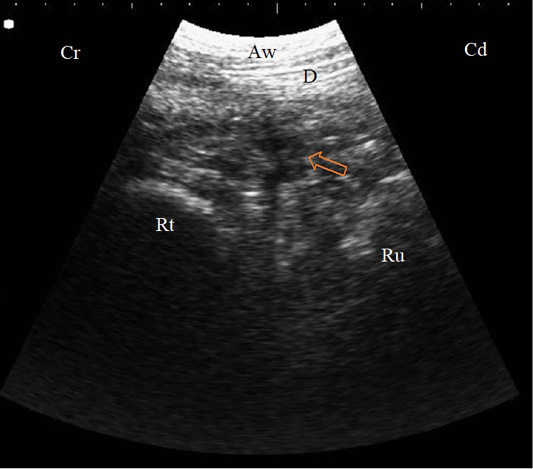

B. Mode sonogram in a case with localized traumatic reticulo-peritonitis. Thickened reticular wall (Rt) separated from the diaphragm (D) with an echogenic fibrinous mass and anechoic exudate (arrow) as imaged from the left 6th ICS, Aw: Abdominal wall, Cr: Cranial, Cd: Caudal.